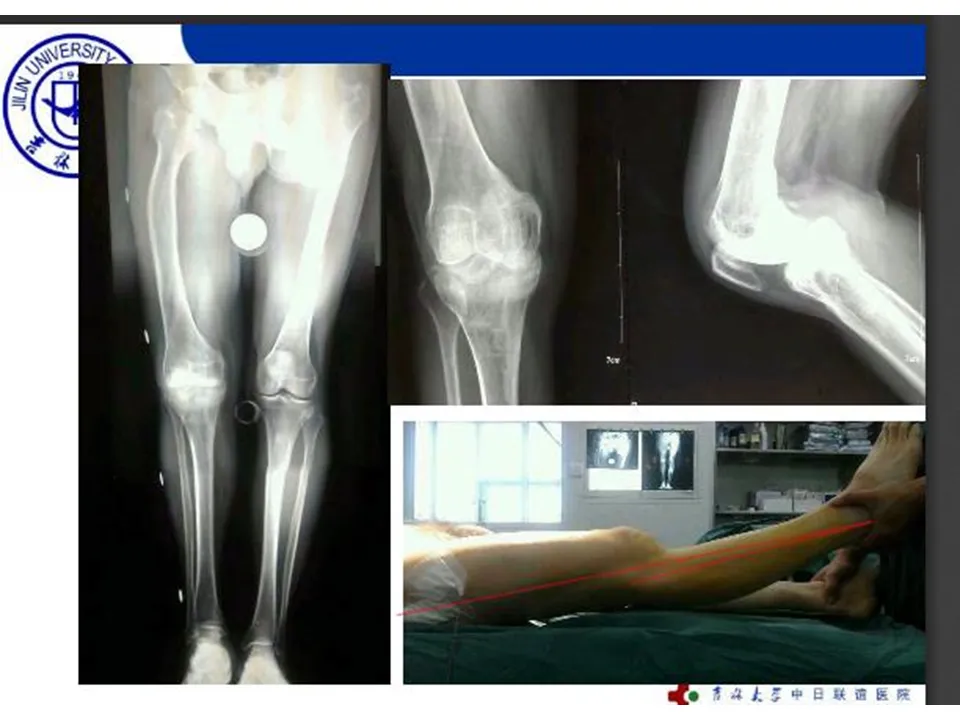

>【骨科PPT】全膝关节置换的截骨原则

【骨科PPT】全膝关节置换的截骨原则